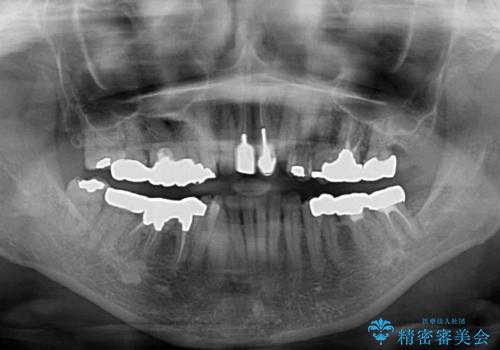

- 全顎的な歯列不正と、銀歯だらけの奥歯を気にして来院された患者様です。

奥歯の銀歯は、セラミッククラウンを装着するには歯の高さが不十分であり、そのままでは矯正治療を行うことが困難であるため、歯冠長延長術を行うこととしました。

また、根管治療の必要な歯がいくつかあるため、歯周外科治療の治癒期間を利用して根管治療を行い、その後インビザラインにて矯正治療を行うこととしました。

矯正治療後にはオールセラミッククラウンにて補綴治療を行うこととしました。